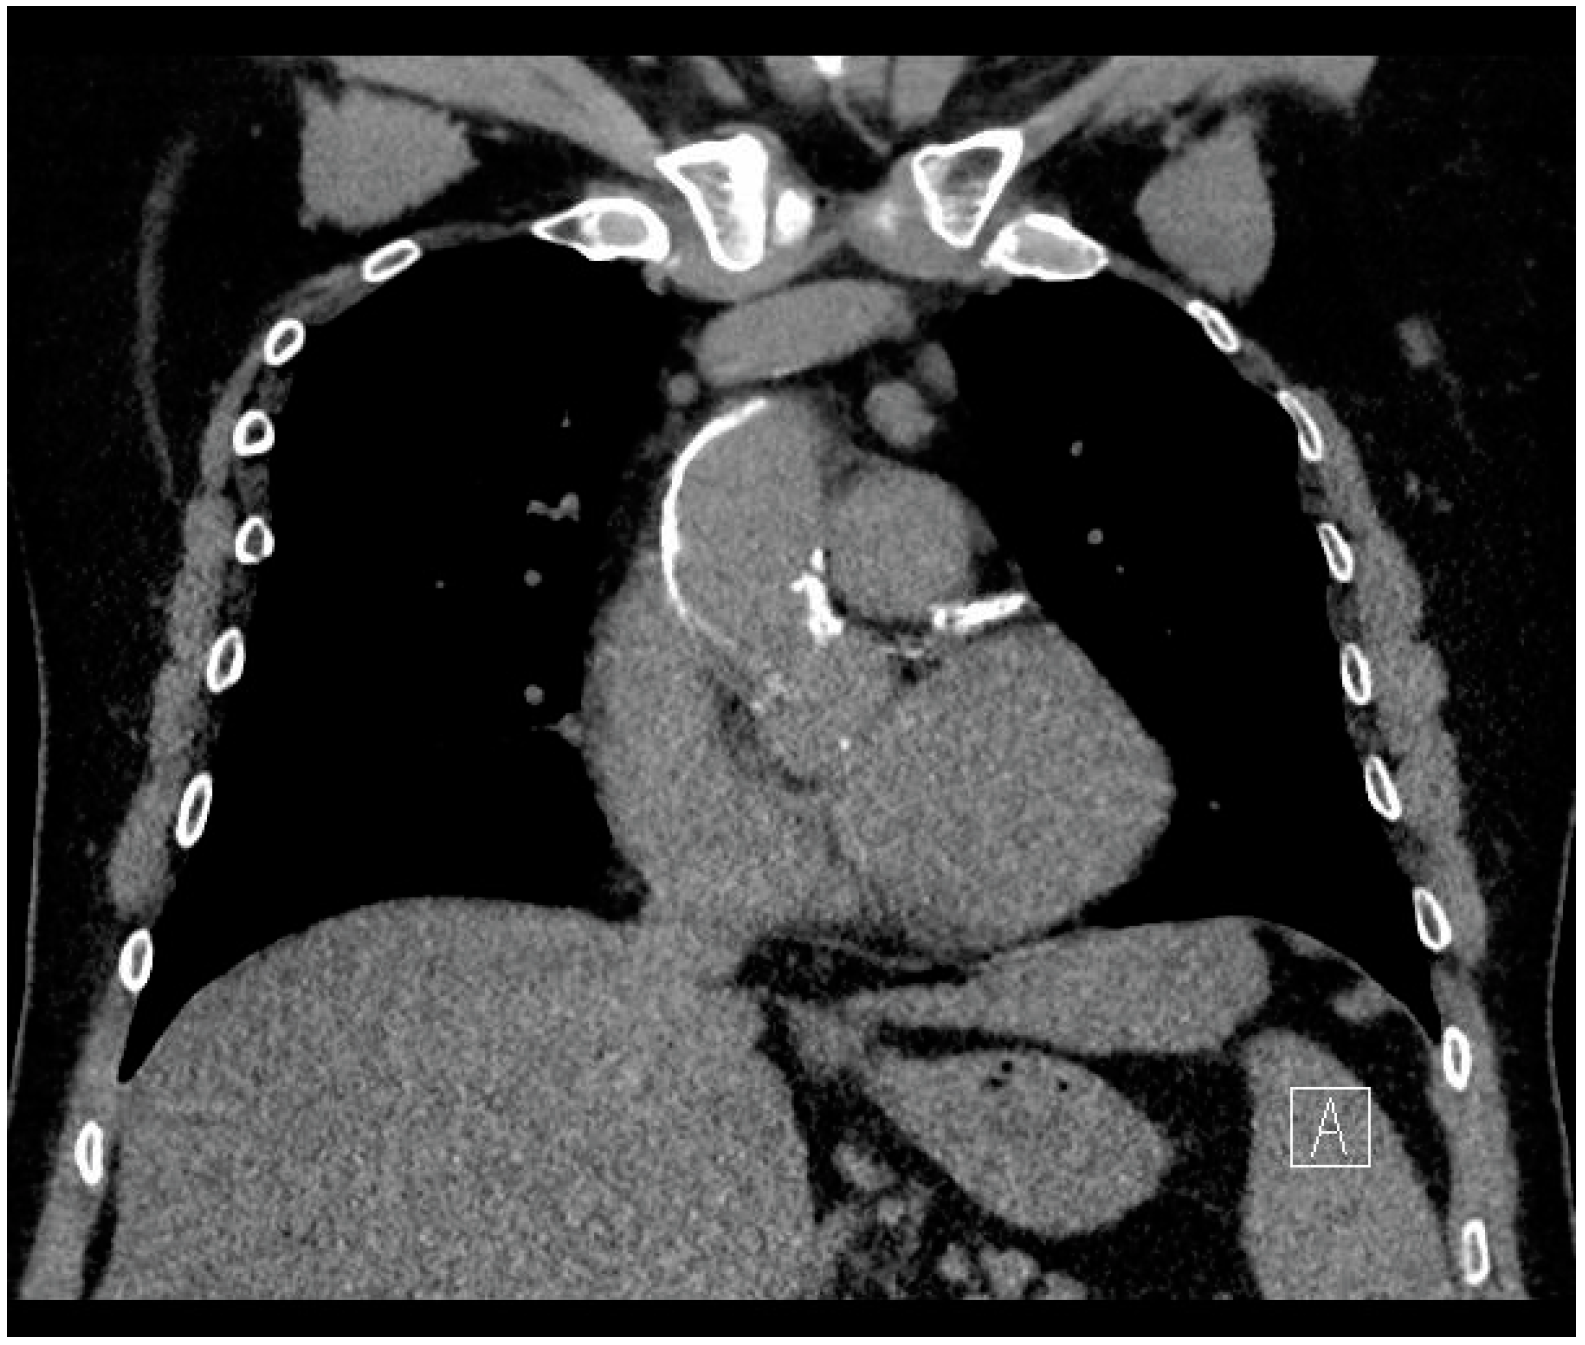

- Undergoing preoperative non-contract CT imaging of the chest.